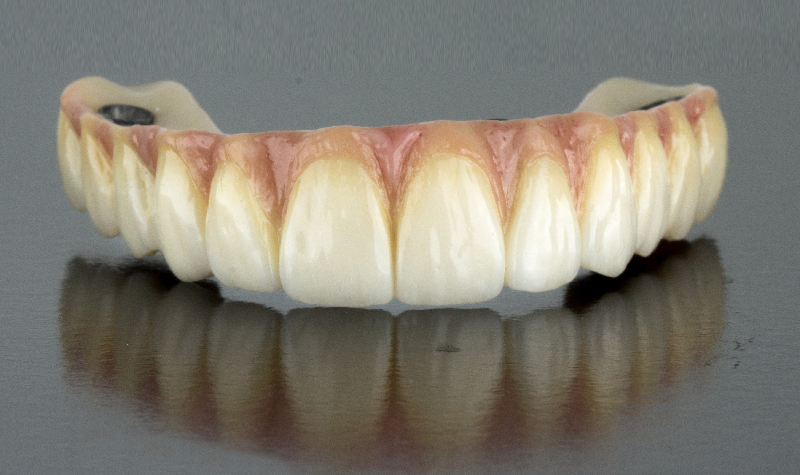

Prótesis híbrida superior de cerámica fija sobre implantes.

Prótesis híbrida superior de cerámica fija sobre implantes